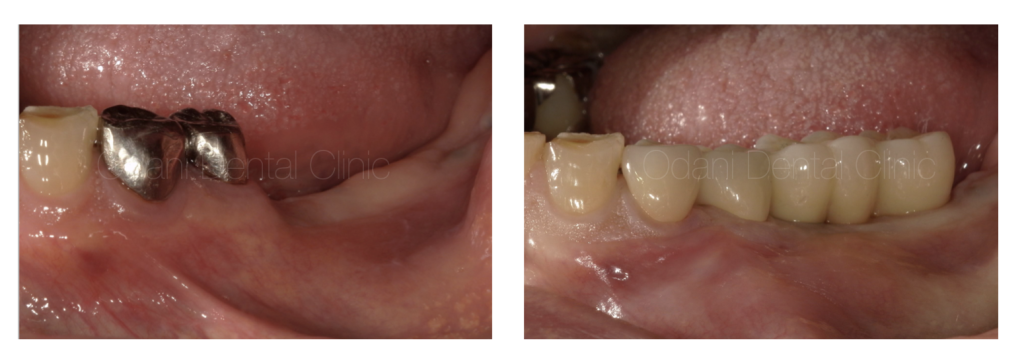

最終上部構造完成時です。段差があった骨のラインは整い、天然の歯とインプラントの歯、そして周囲の歯ぐきも整い、歯ブラシと1本の歯間ブラシのみで清掃が可能となりました。

術前・術後の比較

天然の歯もインプラントの歯も、お手入れしやすいことが長持ちの秘訣です。そして、歯と歯ぐきと骨が連続的に整うことが、見た目と機能とお手入れのしやすさを兼備させるためには必要なポイントとなります。